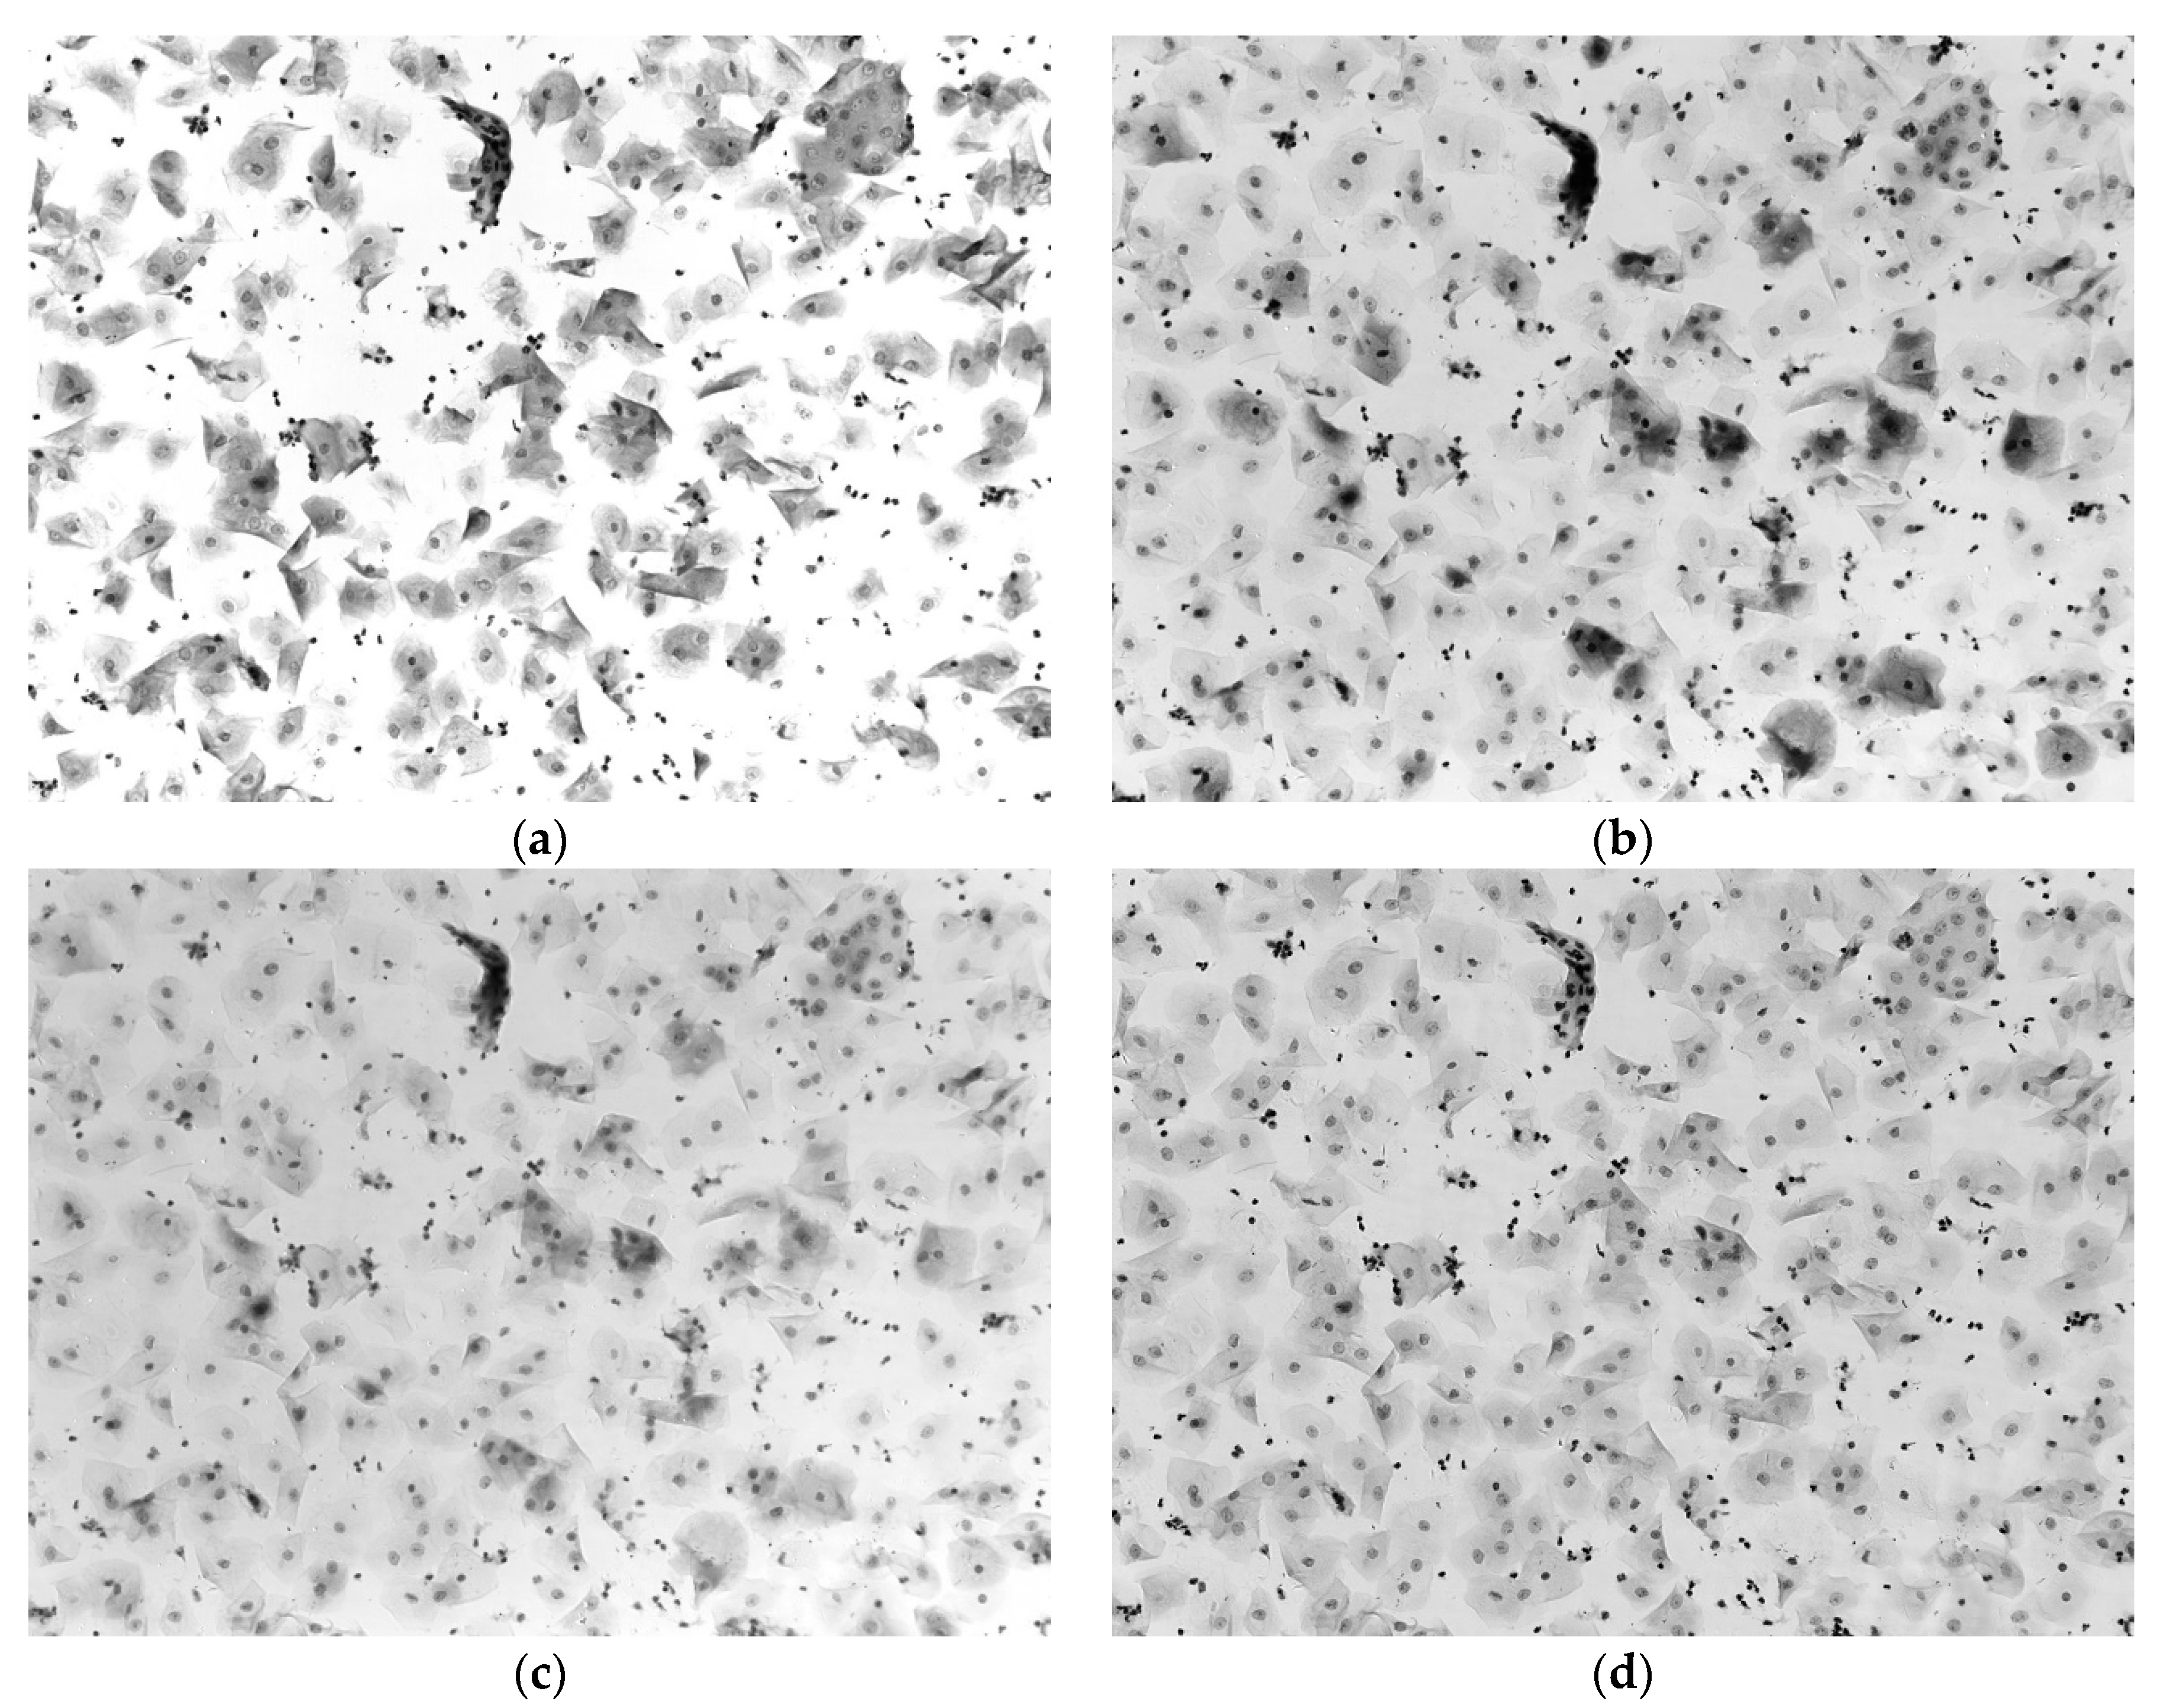

3.1. Pseudo-Color Image Synthesizing and Absorbance Unmixing